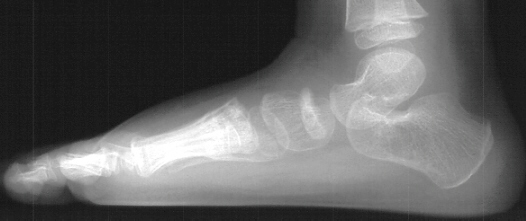

Radiographs of the patient were obtained on her presentation to our clinic. These confirmed the finding of increased radiodensity of the navicular with a flattened appearance to the ossific nucleus. Furthermore they revealed increased density and callus formation in the proximal 1st through 4th metatarsals. This was consistent with multiple non-displaced fractures of the proximal metatarsals secondary to trauma. While Kohler's disease cannot be ruled out in this case, it is more likely that the patient had symptoms produced by her metatarsal fractures. The radiographic appearance of the tarsal navicular almost certainly preceded the acute traumatic event. Therefore, she probably had metatarsal fractures superimposed on irregular ossification of the tarsal navicular giving a clinical picture similar to Kohler's disease.